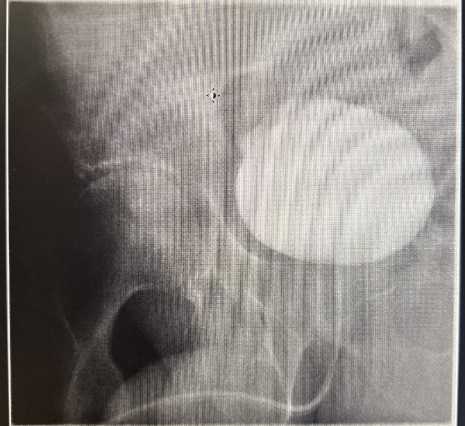

A 70-year-old male with a history of ischemic heart disease managed with a proximal LAD stent, and ongoing treatment with aspirin, atorvastatin, candesartan, and lansoprazole, underwent elective laparoscopic totally extraperitoneal (TEP) right inguinal hernia repair. The procedure was initially uncomplicated. Three years later, he presented with visible haematuria and right-sided abdominal pain. Cystoscopy revealed a 5 mm lesion on the right anterior bladder wall with floating debris, and although imaging excluded urinary obstruction, bowel inflammation raised concerns for possible Crohn’s disease (no previous evidence). The lesion was deemed benign, and he was referred to surgery for evaluation of groin discomfort. Shortly thereafter, he developed a right groin abscess, confirmed on CT and managed twice with ultrasound-guided drainage by interventional radiologist and antibiotics. However, symptoms recurred with ongoing purulent discharge from the suprapubic region. Further imaging revealed displaced mesh embedded within a heterogeneous collection. The patient remained systemically well but required readmission due to persistent wound drainage. A repeat CT (Figure 1) scan showed inflammatory collections in both the inguinal and pelvic regions, with compression of the urinary bladder and associated soft tissue changes. Urgent operative exploration revealed a chronic abscess cavity communicating with the mesh site; the mesh was partially floating and surrounded by infected granulation tissue. The sinus tract was excised, the cavity debrided, and the mesh removed (Figure 2). Postoperatively, the patient developed high-volume serous fluid output through the wound. An urgent cystogram was requested by the urology team after the referral confirmed a vesico-cutaneous fistula originating from the bladder base and tracking to the suprapubic wound (Figure 3). Conservative management with an indwelling urinary catheter was initiated with the urology team’s advice. Despite intermittent haematuria and cloudy discharge, the patient remained clinically stable and was managed with antibiotics. On follow-up cystography, no further leakage was observed, and the fistula was deemed healed, though mild left-sided ureteric reflux persisted (Figure 3). The patient was scheduled for uroflowmetry, and a bladder scan to assess function, and a telephone follow-up was arranged to monitor long-term outcomes. He has also been discussed in both surgical and urological Mortality and Morbidity meetings.

Figure 1. CT abdomen and pelvis (axial and coronal section) demonstrate a well-defined multiloculated abscess collection in the right groin region and pelvis. The collection is associated with inflammatory fat stranding and a linear echogenic band, likely representing migrated or eroded mesh.

Early imaging demonstrated a heterogeneous subcutaneous collection in the right groin region, measuring approximately 43 × 31 mm, containing echogenic linear bands consistent with displaced or degraded mesh. CT imaging confirmed a multiloculated abscess extending from the right iliac fossa to the suprapubic area, with surrounding fat stranding and inflammatory changes, suggestive of chronic infection and mesh-related complications.

Repeat CT of the abdomen and pelvis identified:

• A right pelvic abscess with compressive effects on the bladder (44 × 19 mm)

• A right inguinal collection (38 × 22 mm)

• Signs of phlegmonous changes and a sinus tract extending toward the anterior abdominal wall. These findings raised suspicion of mesh-related erosion and deeper tissue involvement, prompting further urological investigation.